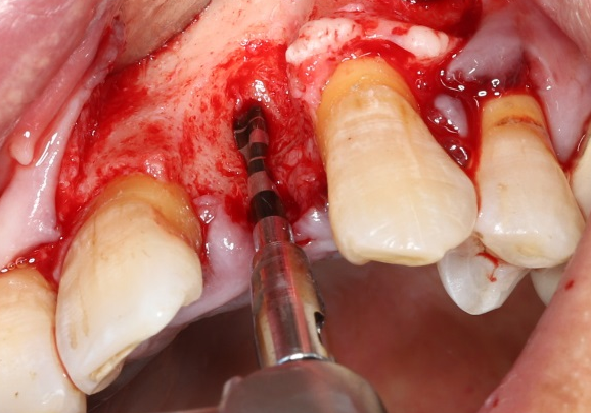

采用不切开骨膜的软组织扩张术——Soft Tissue Extend释放软组织张力

记录翻瓣后原始软组织瓣长度,使用软组织搔刮器(Soft Tissue Extender)冠根向搔刮软组织瓣。

在不切断骨膜的前提下,使用软组织刮治器反复搔刮软组织瓣,可以起到延长软组织瓣的作用。

使用软组织搔刮扩张前后对比:可见在不切断骨膜的前提下,使用软组织搔刮即可获得软组织瓣延长8-9mm。